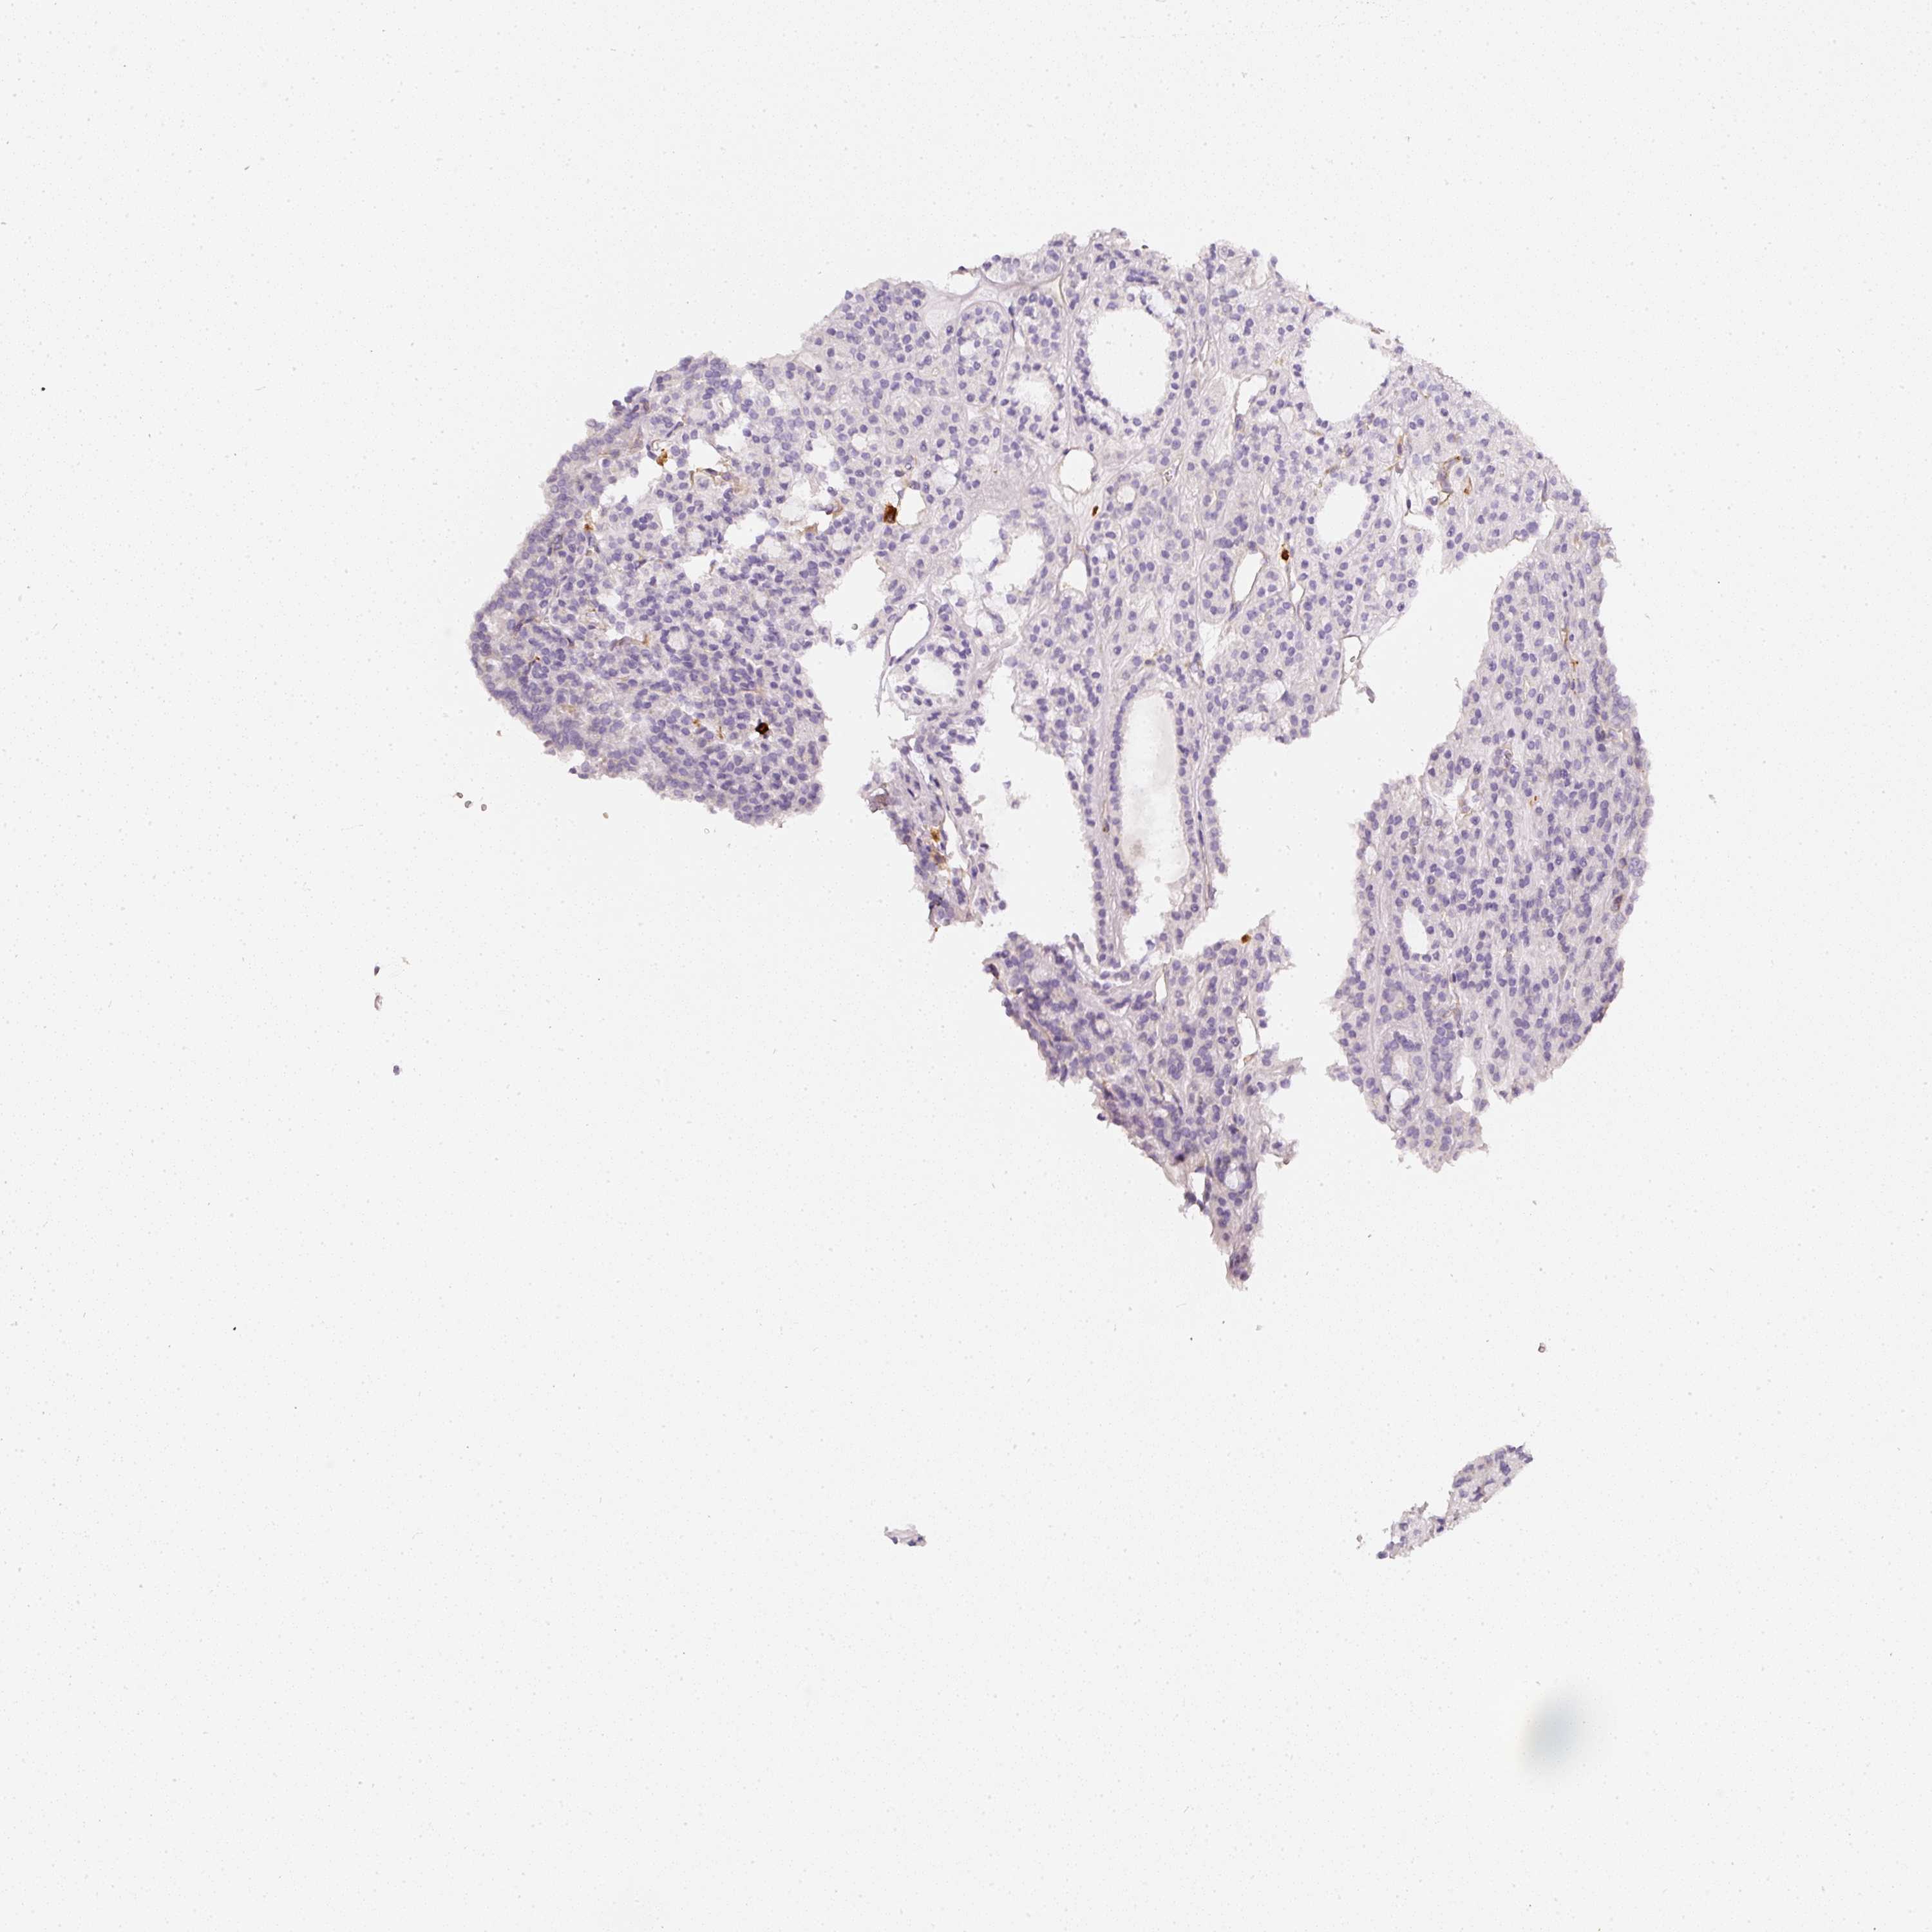

THYROID CANCER - Protein expressioni

A mouse-over function shows sample information and annotation data. Click on an image to view it in a full screen mode. Samples can be filtered based on level of antibody staining by selecting one or several of the following categories: high, medium, low and not detected. The assay and annotation is described here.

Note that samples used for immunohistochemistry by the Human Protein Atlas do not correspond to samples in the TCGA dataset.

Antibody stainingi

Antibody staining in the annotated cell types in the current human tissue is reported as not detected, low, medium, or high, based on conventional immunohistochemistry profiling in selected tissues. This score is based on the combination of the staining intensity and fraction of stained cells.

Each image is clickable and will lead to virtual microscopy that enables deeper exploration of all samples and also displays staining intensity scores, fraction scores and subcellular localization as well as patient and tissue information for each sample.

Antibody HPA018849

Antibody HPA019536

Antibody CAB033987

Staining

High

Medium

Low

Not detected

Intensity

Strong

Moderate

Weak

Negative

Quantity

>75%

75%-25%

<25%

None

Location

Nuclear

Cytoplasmic/membranous

Cytoplasmic/membranous,nuclear

Papillary adenocarcinoma, NOS

Follicular adenoma carcinoma, NOS